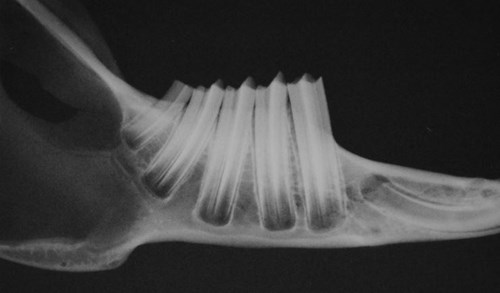

Het gebit van een konijn bestaat uit twee ondersnijtanden, twee bovensnijtanden, twee stifttanden (in de bovenkaak) en 22 kiezen (6 boven en 5 onder aan elke kant). Tussen de snijtanden en de kiezen is een lege ruimte. Er zijn geen hoektanden. De tanden en kiezen lopen nog een heel stuk de kaak in. Bij een konijn is het deel van de tand of kies dat in tandvlees en kaak zit, ook geglazuurd. Er is dus eigenlijk geen verschil tussen de kroon en de wortel en het gedeelte onder het tandvlees wordt ook wel ‘reservekroon’ genoemd. Voor de duidelijkheid gebruiken we hier toch de term ‘wortel’ voor het onderste deel van de tand of kies. Helemaal onderaan zit een open gedeelte met het einde van het wortelkanaal.

Röntgenfoto van de kiezen in de onderkaak. Rechts is de wortel van de snijtand te zien.

Dat konijnen niet tot de knaagdieren gerekend worden, komt onder andere doordat ze achter hun twee bovenste snijtanden nog twee kleine tandjes hebben staan, de stifttanden. Knaagdieren hebben die niet. De ondertanden van het konijn staan precies achter de boventanden en komen tegen deze stifttanden aan.